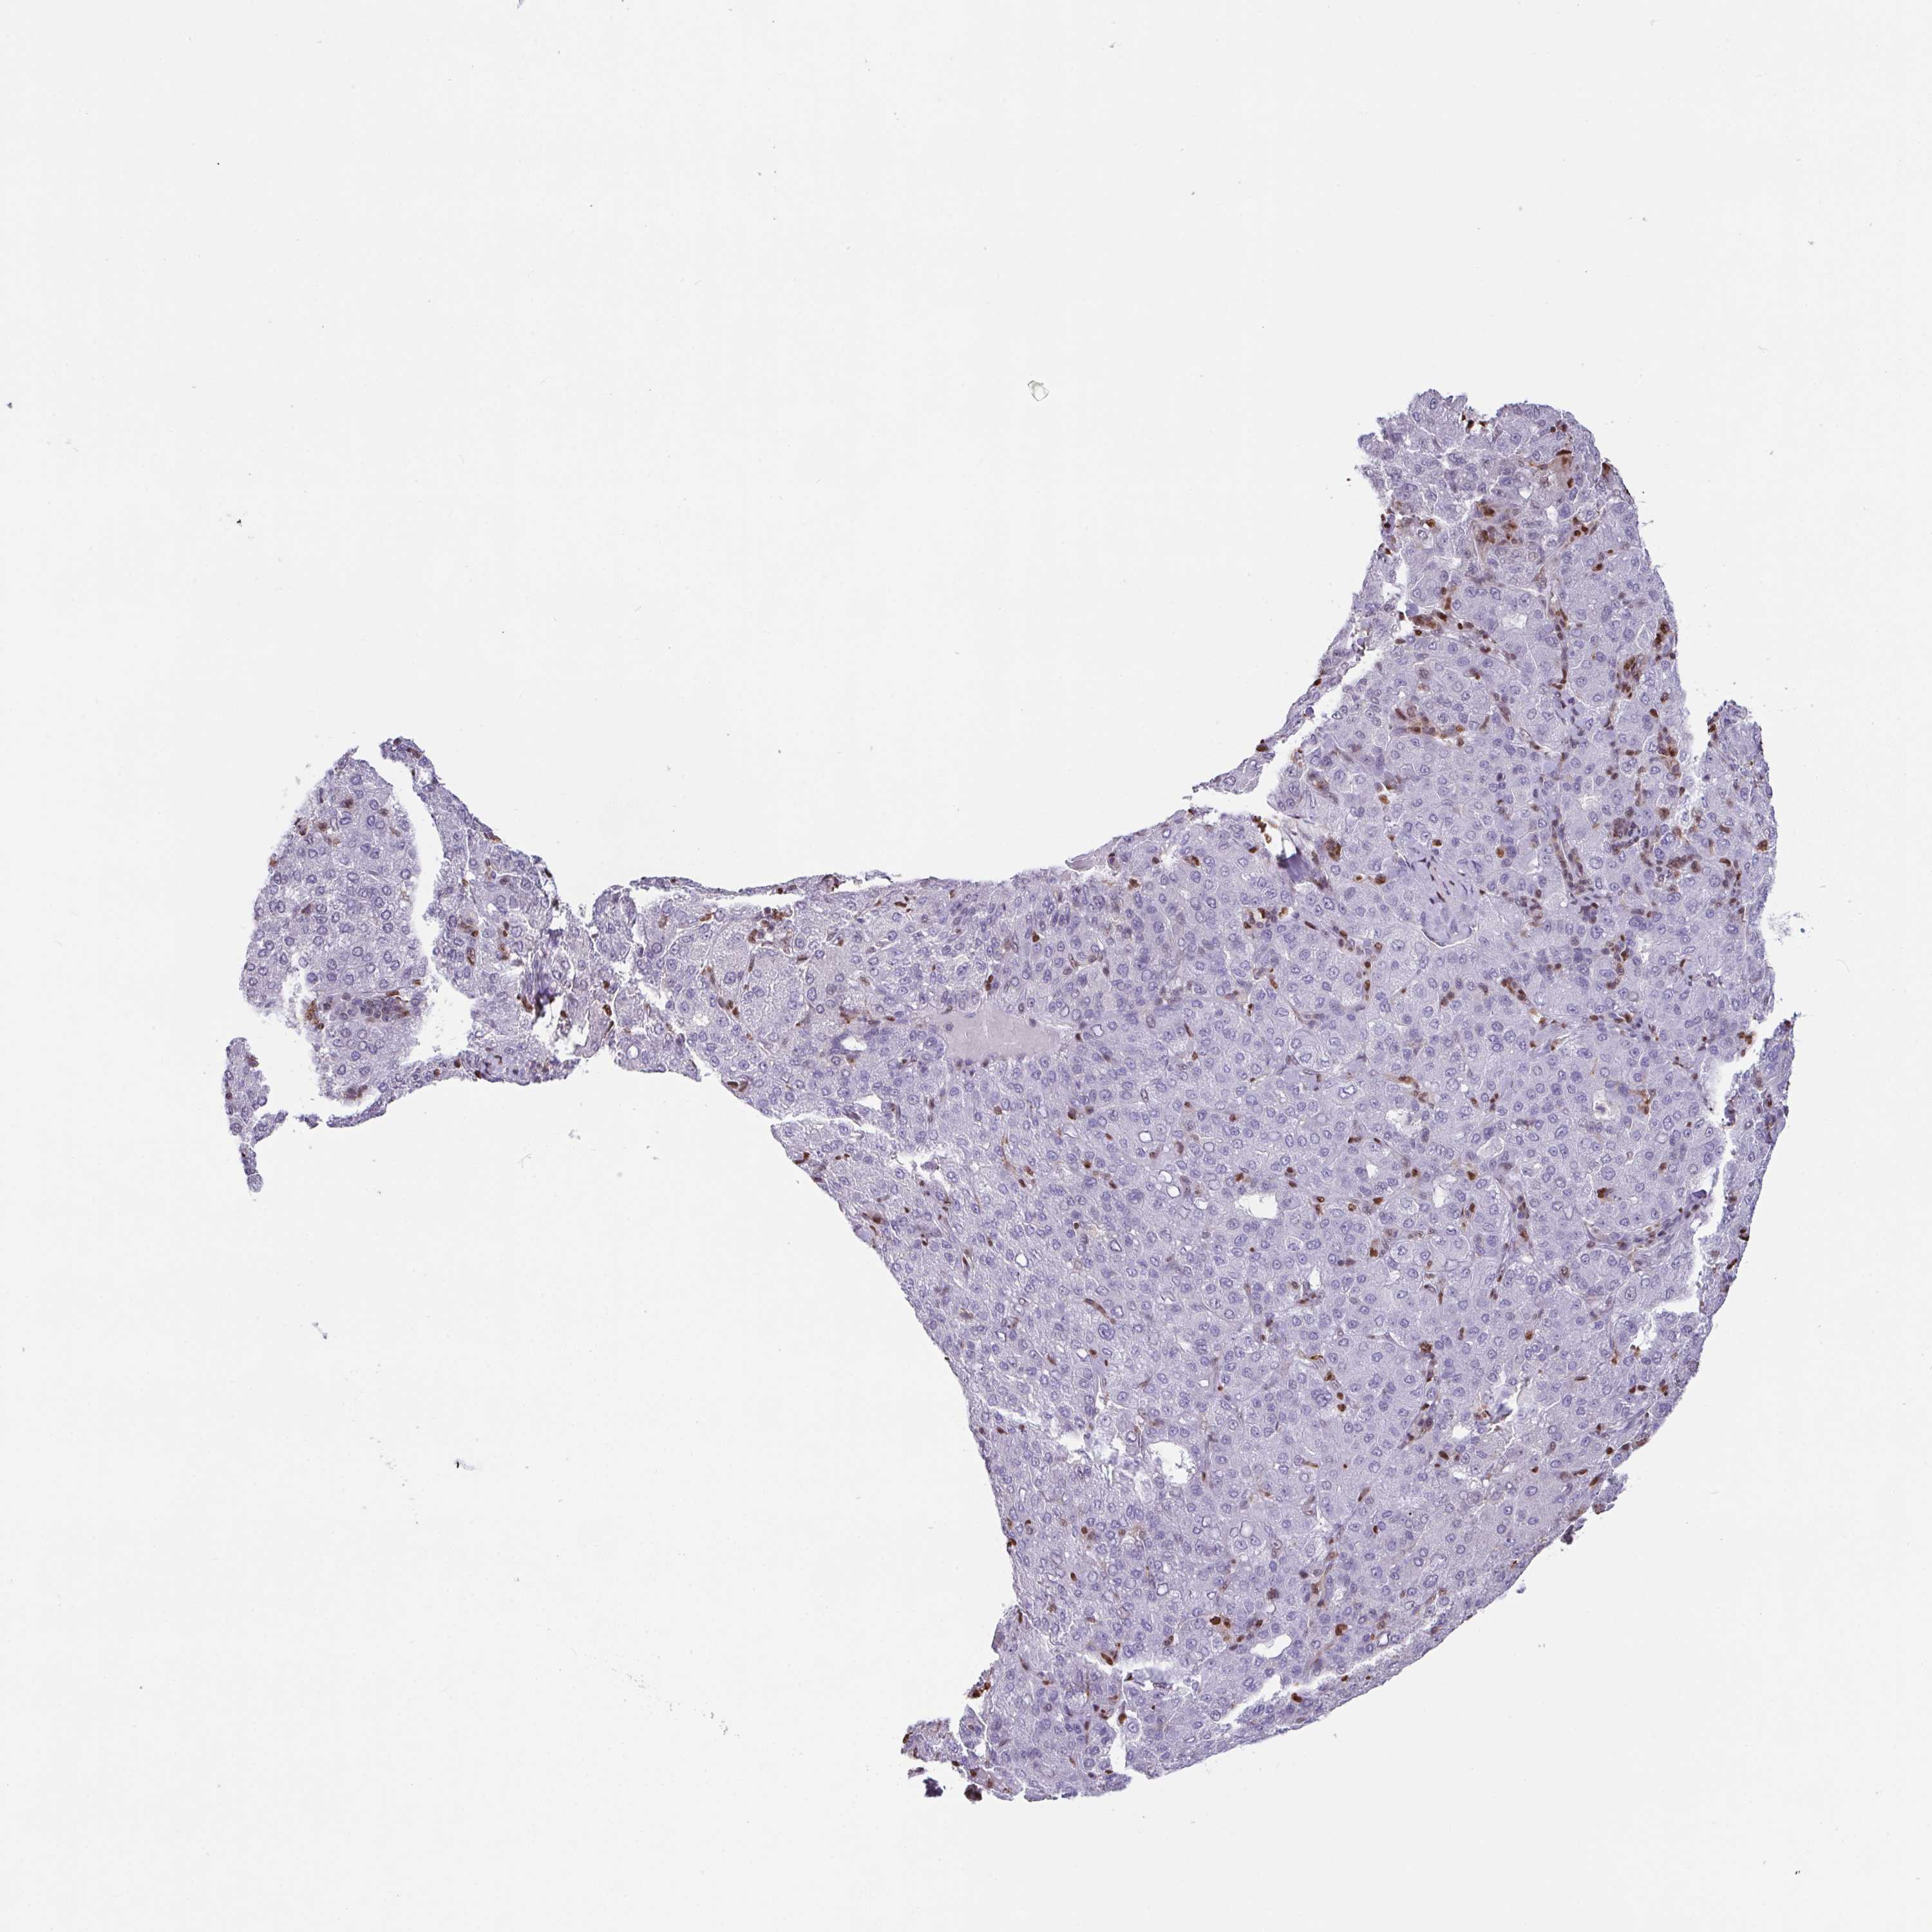

LIVER CANCER - Protein expressioni

A mouse-over function shows sample information and annotation data. Click on an image to view it in a full screen mode. Samples can be filtered based on level of antibody staining by selecting one or several of the following categories: high, medium, low and not detected. The assay and annotation is described here.

Antibody stainingi

Antibody staining in the annotated cell types in the current human tissue is reported as not detected, low, medium, or high, based on conventional immunohistochemistry profiling in selected tissues. This score is based on the combination of the staining intensity and fraction of stained cells.

Each image is clickable and will lead to virtual microscopy that enables deeper exploration of all samples and also displays staining intensity scores, fraction scores and subcellular localization as well as patient and tissue information for each sample.

Antibody HPA046777

Staining

High

Medium

Low

Not detected

Intensity

Strong

Moderate

Weak

Negative

Quantity

>75%

75%-25%

<25%

None

Location

Nuclear

Cytoplasmic/membranous

Cytoplasmic/membranous,nuclear

Carcinoma, Hepatocellular, NOS